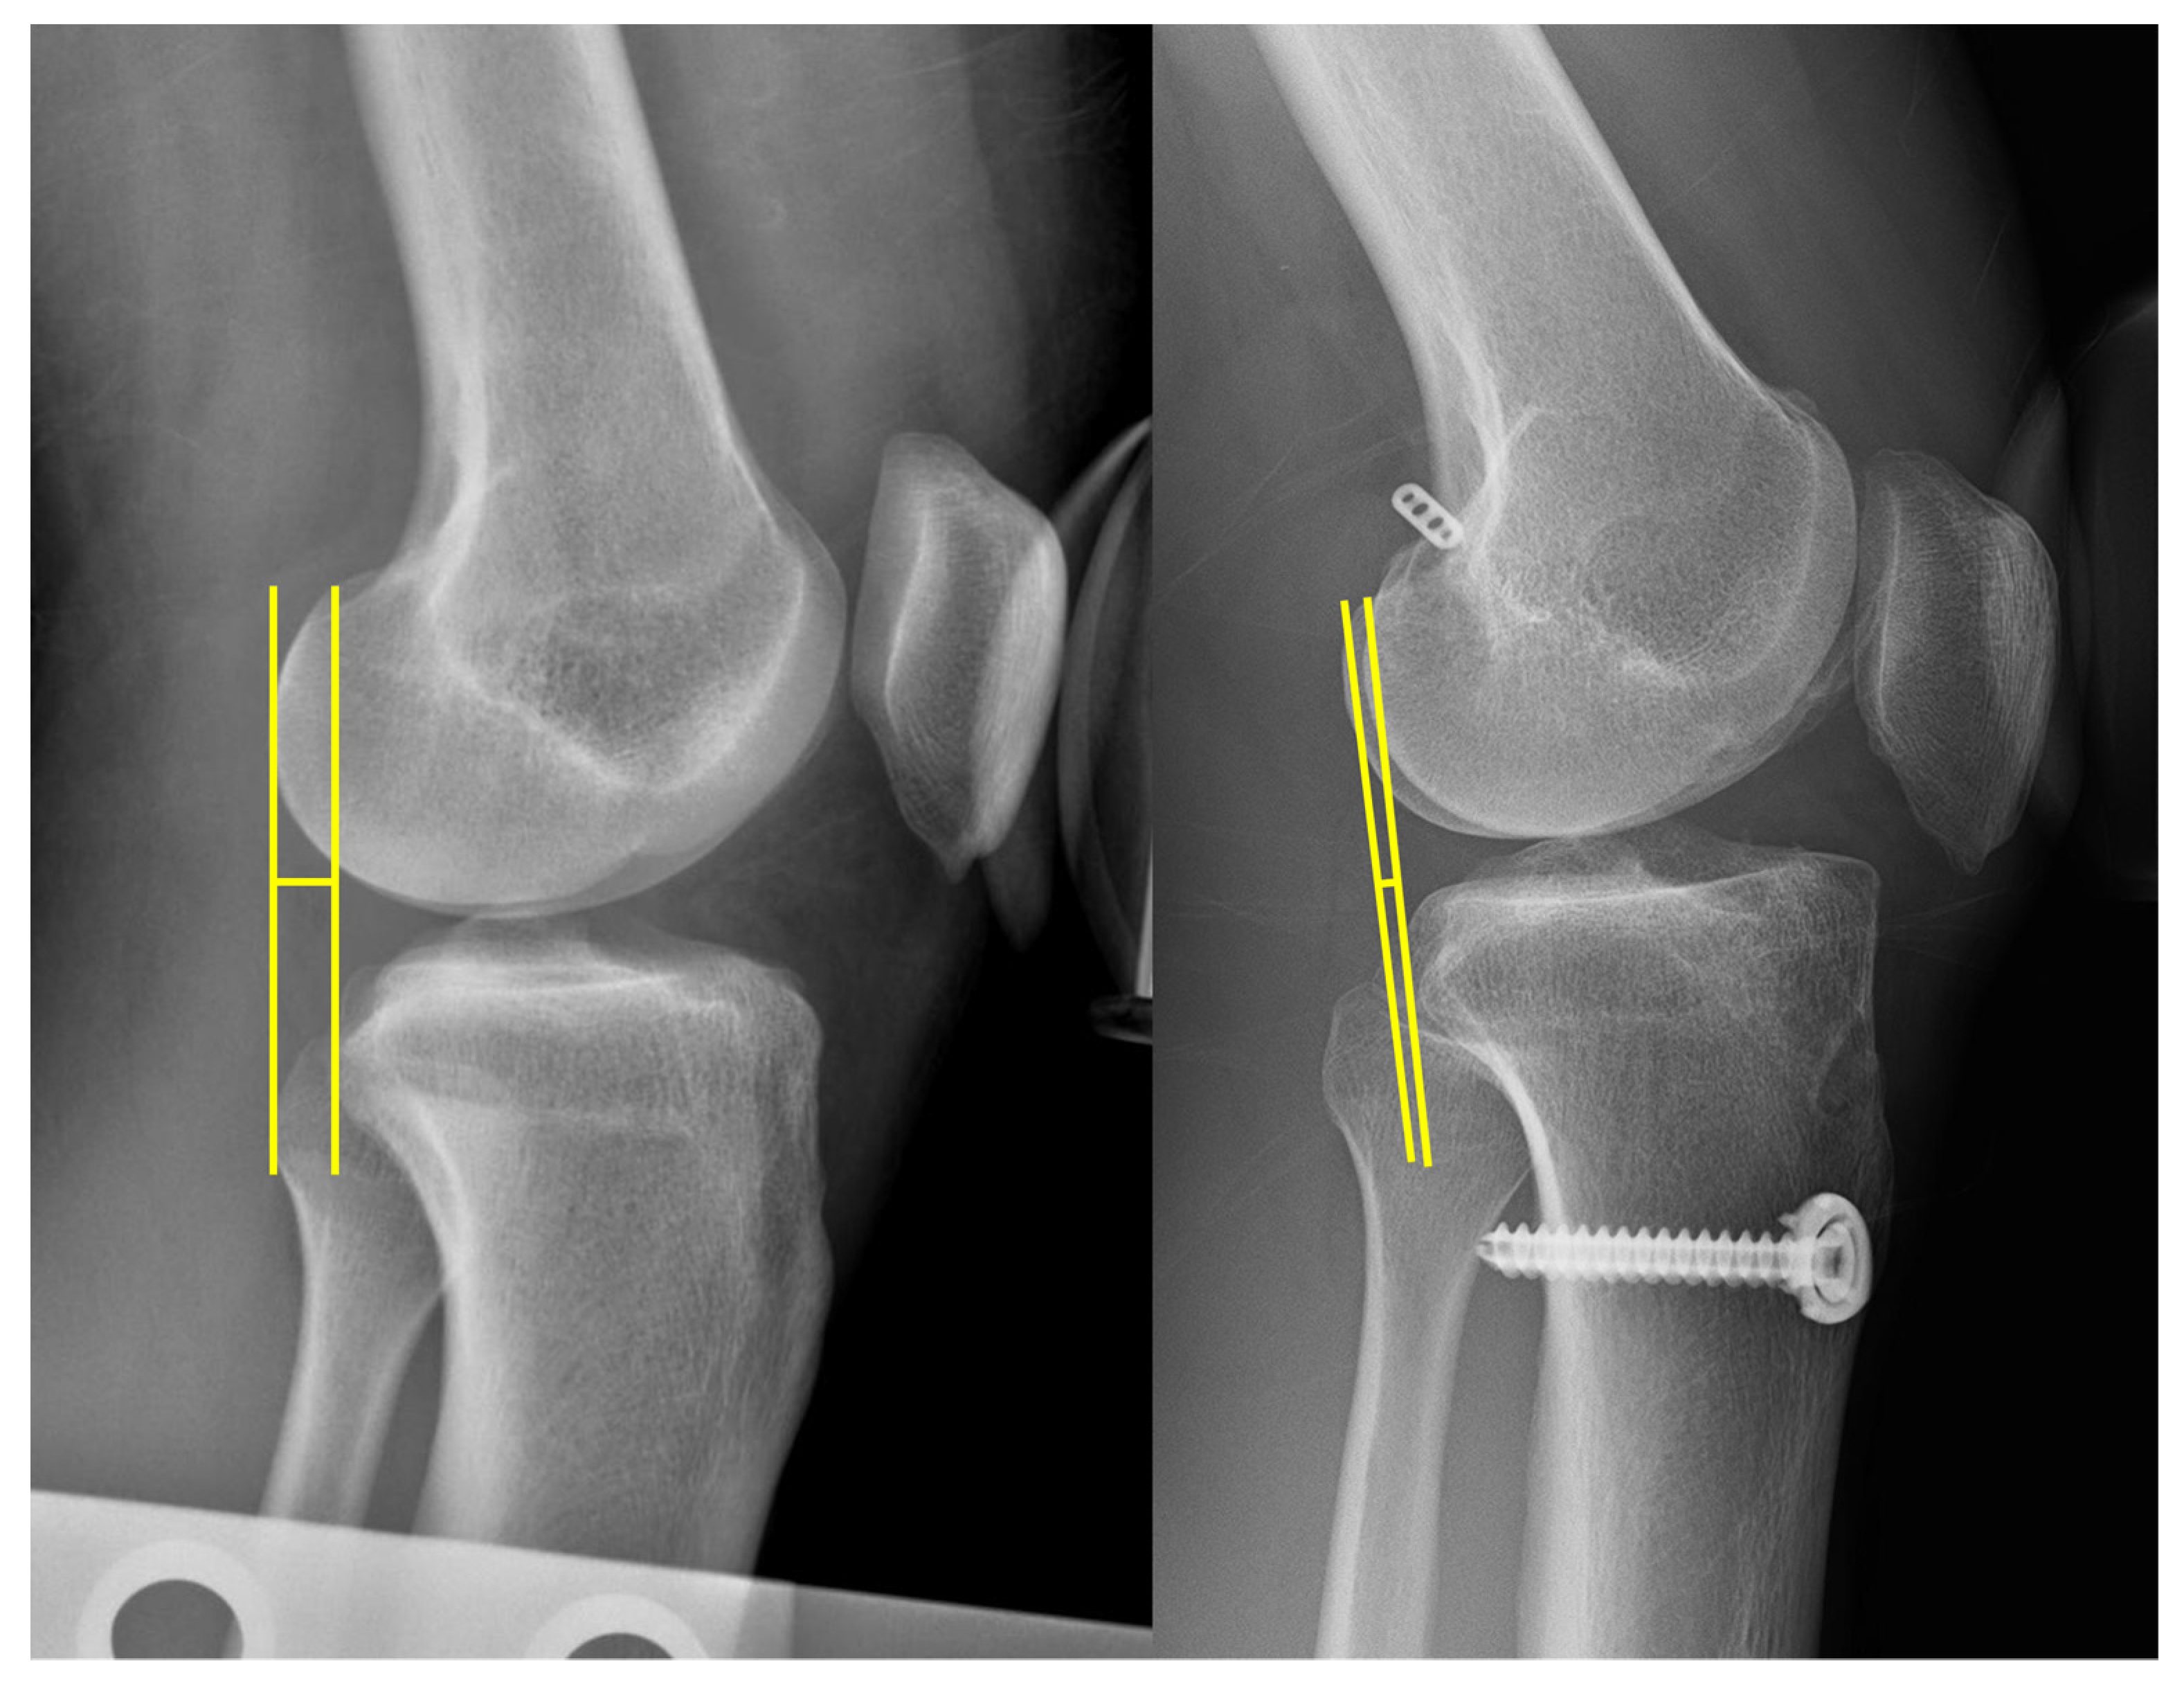

2.3. Clinical and Radiographic Evaluation

- Jacobsen, K. Stress radiographical measurement of the anteroposterior, medial and lateral stability of the knee joint. Acta Orthop. Scand. 1976, 47, 335–344. [Google Scholar] [CrossRef]

| STSD, mm | 6.0 ± 3.4 | 2.3 ± 2.2 | <0.001 |

| STSD, mm | 5.9 ± 3.0 | 6.3 ± 4.3 | 0.68 |

| STSD, mm | 2.4 ± 2.2 | 2.0 ± 2.2 | 0.319 |

| Change in STSD (pre to post), mm | 3.5 ± 3.5 | 4.3 ± 4.4 | 0.295 |